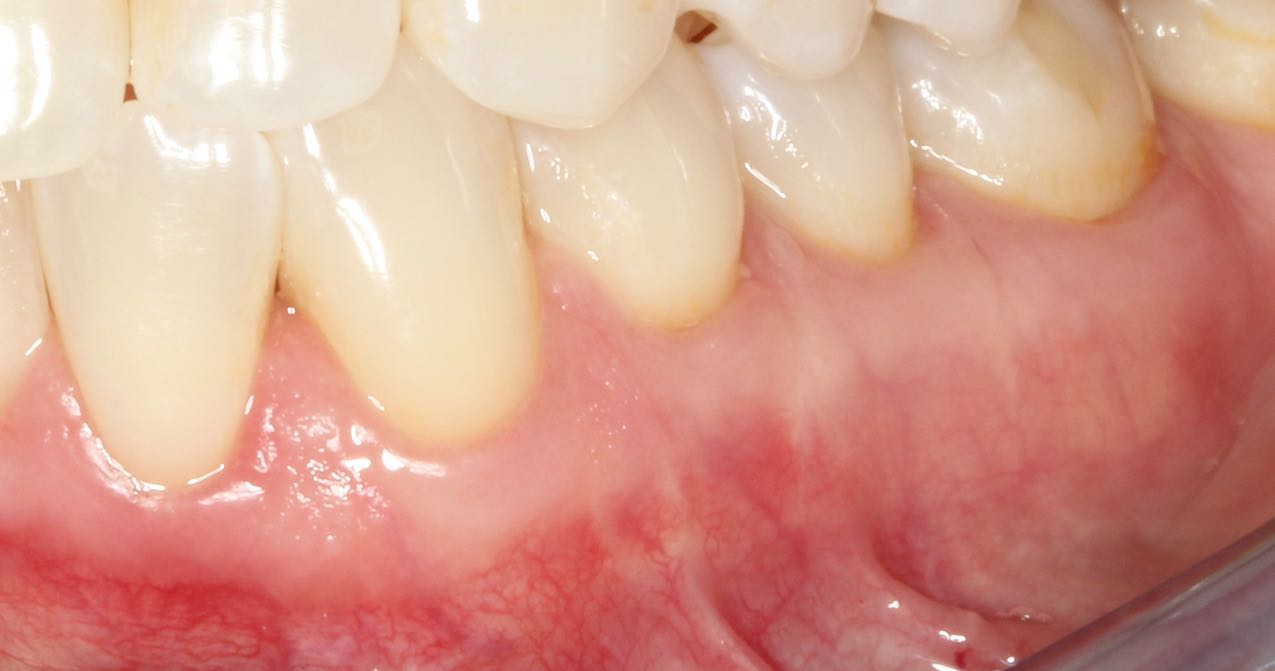

Connective Tissue Gingival Grafting for Gingival Recession